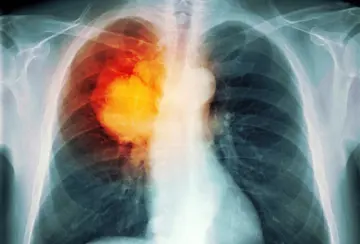

داروسازی - صفحه 15